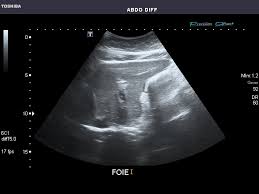

복부 초음파는 초음파(ultrasound)를 이용해 복부 내 장기들의 상태를 확인하는 비침습적 검사 방법입니다. 방사선을 사용하지 않아 인체에 해롭지 않고, 고통 없이 실시간으로 복부 장기들을 관찰할 수 있다는 점에서 가장 기본적이면서도 효과적인 진단도구로 평가받습니다.

초음파 탐촉자(Probe)에서 발생한 고주파 음파가 인체 내부 장기에 부딪혀 반사되며, 복부 초음파로 알 수 있는 것은 바로 이 반사파를 영상화해 간, 담낭, 췌장, 비장, 신장(콩팥), 방광, 대동맥, 림프절 등의 상태를 분석하게 됩니다.